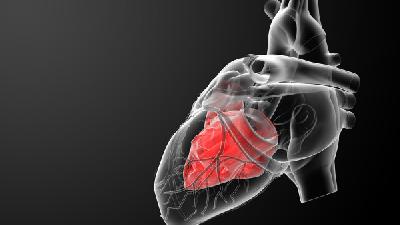

心律失常的原因

心律失常对于现实生活中的人们来说是一类危害比较大的疾病,而此病的发病率也是很高的,许多朋友都通过了解心律失常的原因来做好相关的预防措施,那么下面就来了解一下心律失常的原因吧。1、药物作用:某些药物的服用,可影响心脏收缩而导致心律失常。另外,安眠药中毒等也可引起严重心律失常。这就是引起心律失常的原因之一。2、个人生活:其实正常人也可出现心律失常的状况,若过度疲...

常见的诱发心律失常的原因有哪些

心律失常对我们生活的影响是非常的大的,但是由于人们对引起心律失常的原因不是很了解,所以病情就没有得到控制,那常见的诱发心律失常的原因有哪些呢?下面就让我们一起来进一步的了解下诱发心律失常的原因。1、药物作用:某些药物的服用,可影响心脏收缩而导致心律失常。另外,安眠药中毒等也可引起严重心律失常。这是引发心律失常的原因。2、个人生活:其实正常人也可出现心律失常的...

生活中有很多导致心律失常发生的病因

在内科疾病中,心律失常实属比较严重的一种,一般会影响到患者的身体。而我们如果再不重视引起心律失常的原因,就可能会导致此病的频繁出现。因此大家要提前了解心律失常的原因,这样才能及时防御好此病。下面就来介绍心律失常的原因有哪些情况。心律失常的原因有:1、运动运动时通过降低副交感神经张力,增加交感神经张力,会使心率增快,房室传导改变,心肌耗氧量增加,诱发心律失常。...